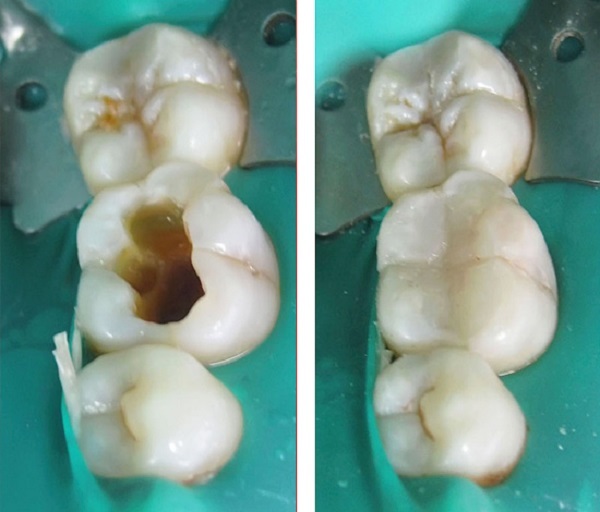

Пломбирование каналов: фото до и после